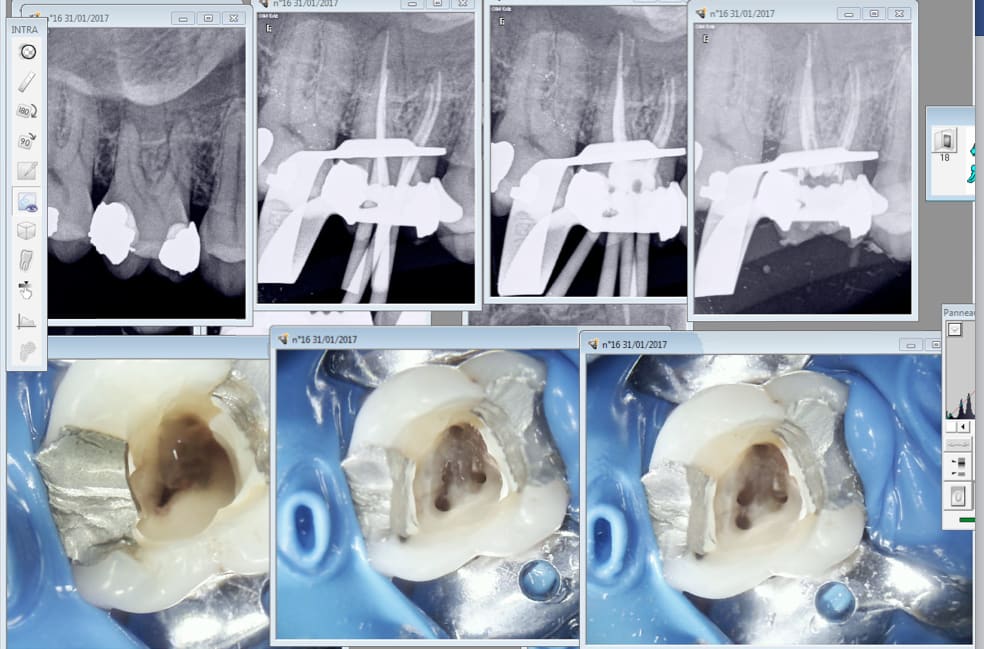

Nan, là je fais le malin!

ça va Enlaye, t'es toujours vivant?-))) T'as vu? les prépas et l'occlusion aux petits oignons! Eh! Y en a là dedans ;-)))

En plus c'est pas des chinoiseries, non môsieur, c'est du made in France!

En revanche la patiente est polonaise, on peut pas gagner à tous les coups.